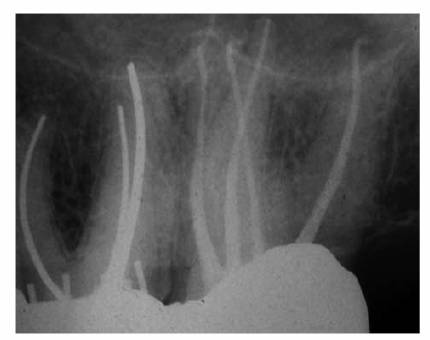

In most cases, an endodontic procedure should not be initiated without

angulations of the suspected tooth (Figures 19-24A

and B).

Comparing varied views is essential in diagnosing the presence of additional

roots, anatomic configurations, anomalies, and other unusual circumstances that

may complicate the treatment.

Figure 19-24A and B: (A) Pretreatment radiograph of a mandibular premolar shows one canal. (B) A second radiograph taken from an angulation of 15 degrees from the mesial discloses a second root.